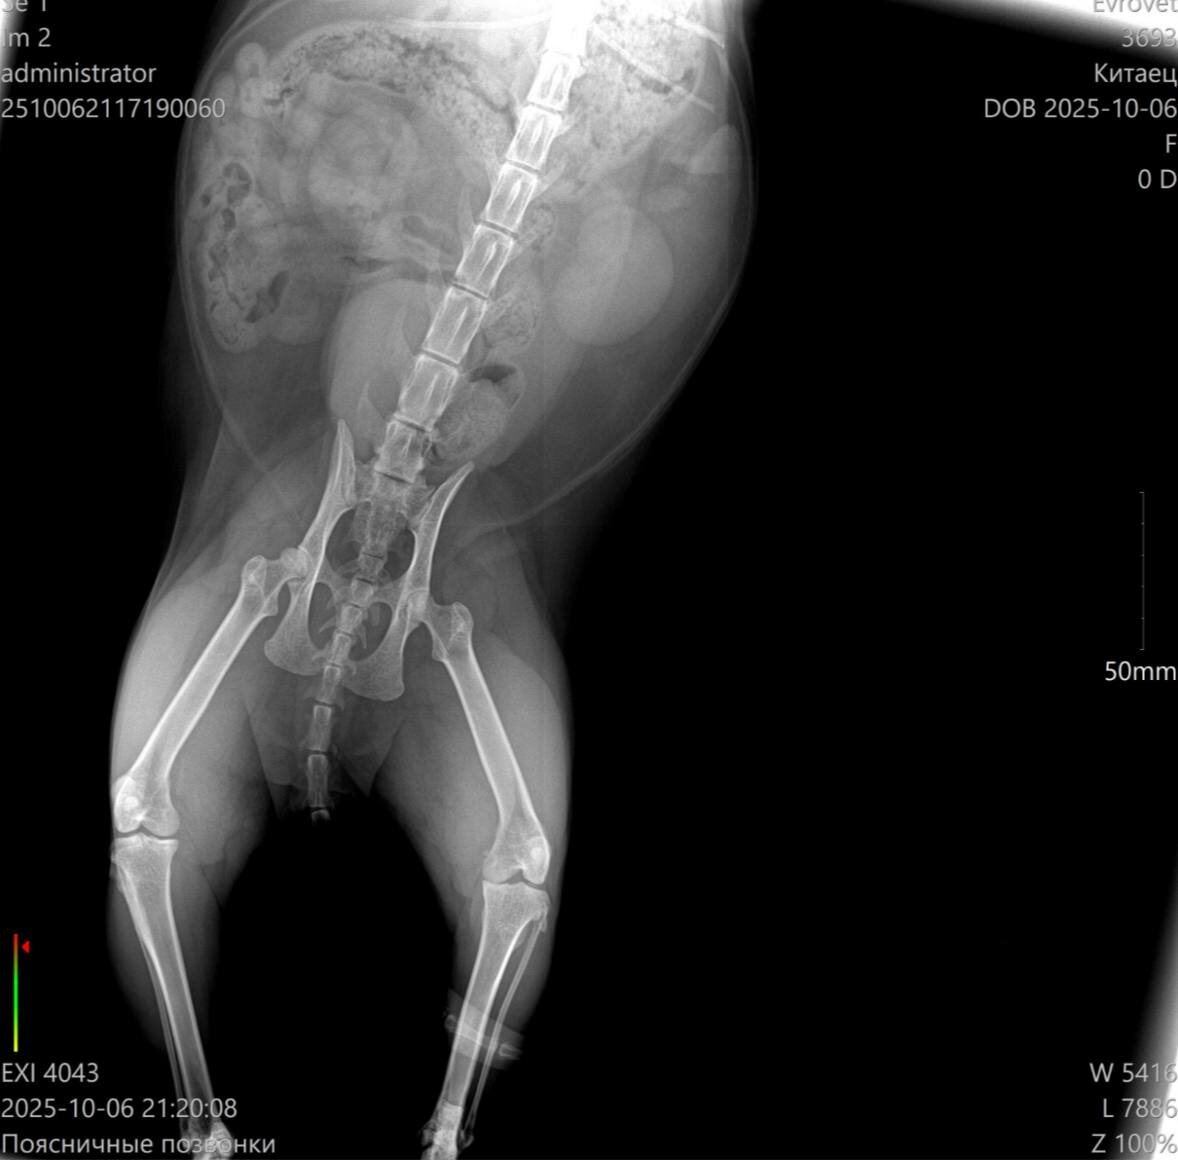

Сделали снимок, исключили переломы. Оказалось - ушиб. Но сильный.

Я подозреваю, что из-за телосложения повышенного питания и страха, Китаец упал с дерева неудачно.

Видно было, что ему больно.